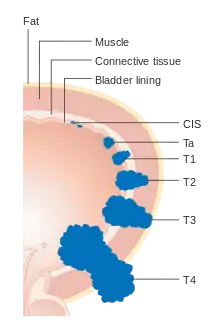

Staging

Bladder cancer is staged (classified by the extent of spread of the cancer) and graded (how abnormal and aggressive the cells appear under the microscope) to determine treatment and predict outcomes. Staging is usually performed with transurethral resection of bladder tumor (TURBT) and radiologic imaging (CT and MRI). Papillary tumors confined to the mucosa or which invade the lamina propria are classified as Ta or T1. Flat lesions that do not invade the basement membrane of the bladder mucosa are termed Tis (in situ). All three categories (Tis, Ta and T1) are grouped together as non-muscle invasive disease for therapeutic purposes and in most cases they are offered cystoscopic resection with TURBT without the need for radical resection of the entire urinary bladder. Tumors in the remaining categories (T2, T3 and T4) are termed muscle-invasive disease and are associated with less favorable prognosis.[56]

- Ta Non-invasive papillary carcinoma

- Tis Carcinoma in situ ('flat tumour')

- T1 Tumour invades subepithelial connective tissue

- T2a Tumour invades superficial muscle (inner half of the detrusor muscle)[77]

- T2b Tumour invades deep muscle (outer half of the detrusor muscle)[77]

- T3 Tumour invades perivesical tissue:

- T3a Microscopically

- T3b Macroscopically (extravesical mass)

- T4a Tumour invades prostate, uterus or vagina

- T4b Tumour invades pelvic wall or abdominal wall